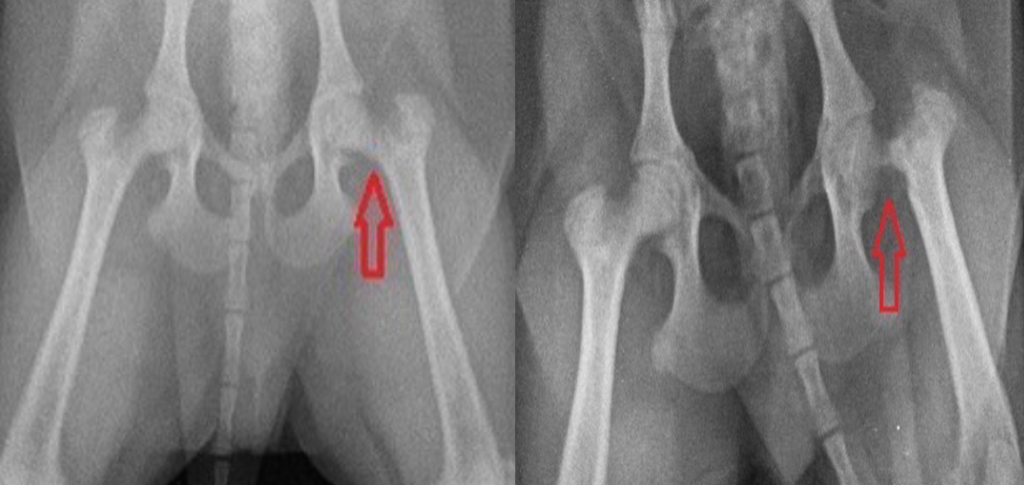

- Рентген тазобедренного сустава (на снимке заметны изменения формы головки бедра).

(из практики Максима Александровича Кардаша)